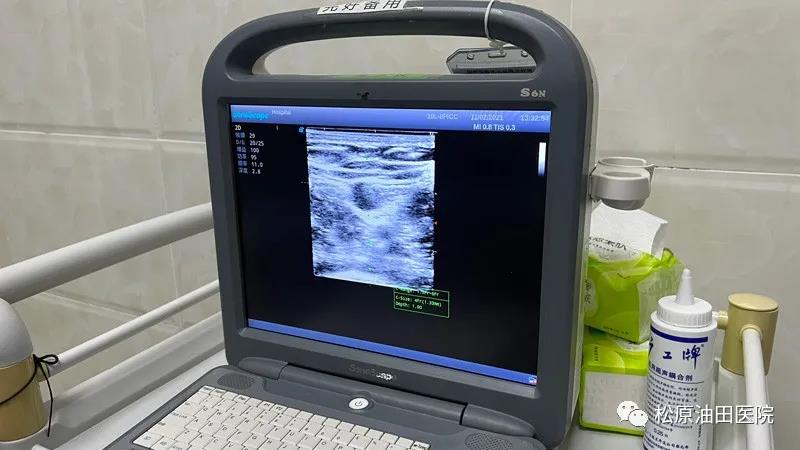

在谈到超声引导下采用塞丁格(MST)穿刺技术PICC置管的优势时,松原吉林油田医院PICC门诊护士长刘晓明介绍说:“超声引导下PICC置管可以直观地显示血管的位置和解剖结构,增加穿刺的精准性,具有实时引导、全程可见、穿刺时间短等优势。不仅能减轻穿刺患者的痛苦,同时为护理人员提供了一种安全有效的输液途径。超声引导下采用塞丁格穿刺技术完成PICC置管将传统的置管部位从肘窝上移到上臂,减少了肢体活动对导管的摩擦和牵拉,减少了导管在血管内移动对血管壁的刺激,从而减少了导管相关性感染及血栓等并发症,对导管的长期留置非常有利,能为患者提供中期至长期的静脉输液治疗,PICC导管留置时间可长达一年,解决了外周血管条件差病人的输液难题,能满足肿瘤病人常规化疗多个疗程的需要。”